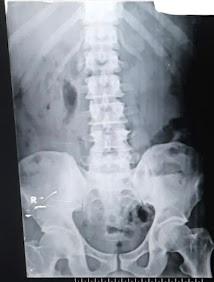

plain xray kub-

usg abdomen- ? rt sided kidney emphysematous pyleonephritis, lt sided kidney subcapsular collection noted.